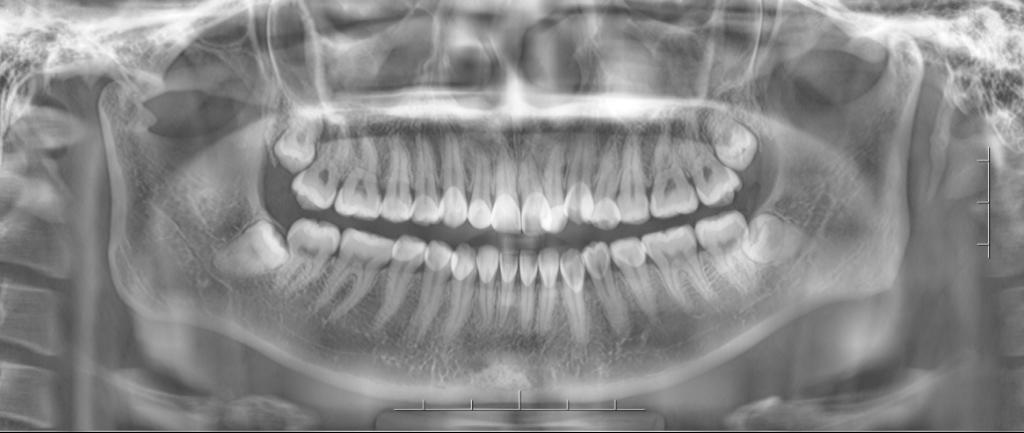

智齿萌出

1、阻生齿长轴与第二磨牙长轴关系分类:垂直阻生、近中阻生、水平阻生、倒置阻生、远中阻生、舌向阻生和颊向阻生。

2、阻生齿相对于第二磨牙拾平面的位置关系分:高位阻生、中位阳生和低位阻生。

3、阻生齿和下颌支前缘相对位置关系分为以下三类:

Ⅰ类:阻生牙牙冠的近远中径完全位于下颌支前缘的前方。

Ⅱ类:一半以内的阻生牙牙冠的近远中径位于下颌支内。

Ⅲ类:一半以上的阻生牙牙冠的近远中径位于下颌支内。